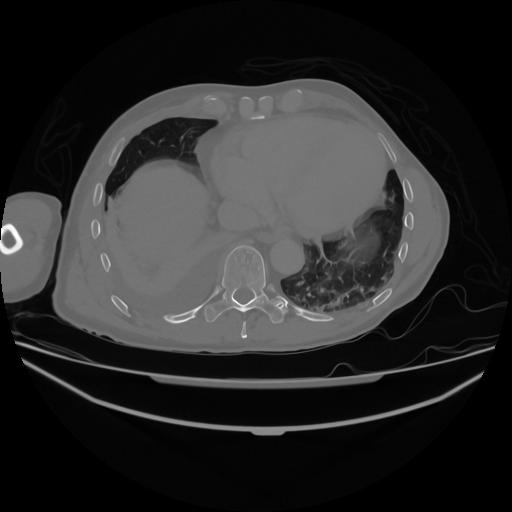

5 CUERPO,CE,Vol,1.0,CUERPO,,